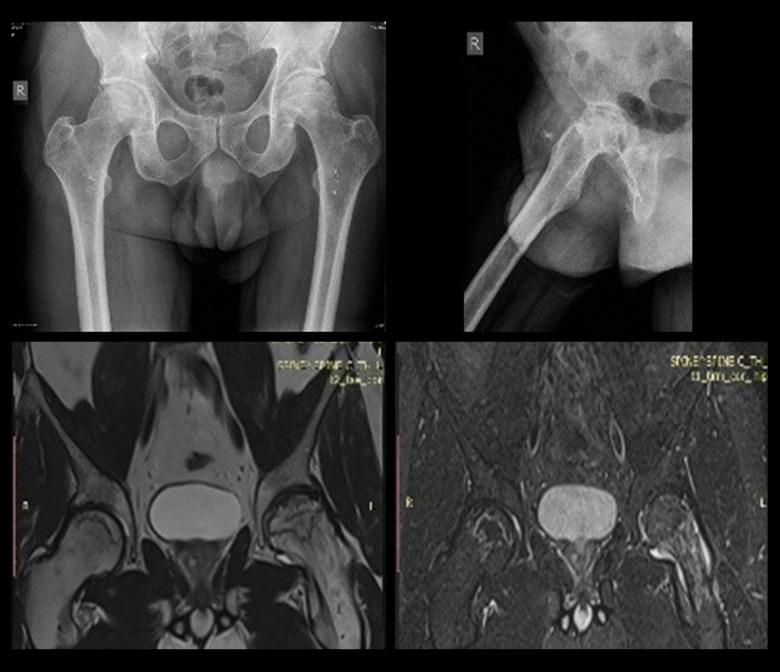

BACKGROUND Avascular necrosis (AVN) of the femoral head can result from high-dose corticosteroid therapy. Given that severe COVID-19 pneumonia patients respond positively to corticosteroids, this study aimed to explore the incidence of femoral head AVN associated with corticosteroid therapy in 24 patients diagnosed with severe COVID-19 at a single center. MATERIAL AND METHODS The study included 24 patients who were diagnosed with severe acute respiratory syndrome coronavirus 2 (SARS-CoV-2) infection through real-time reverse transcription polymerase chain reaction test (rRT-PCR) and with COVID-19 pneumonia via high-resolution computed tomography (HRCT). Moderate cases received 2×4 mg Dexamethasone while severe cases were also administered with 3×40 mg Methylprednisolone. Diagnosis of femoral head AVN was confirmed with magnetic resonance imaging (MRI) and radiographs, which was subsequently treated by a total hip arthroplasty (THA) or a core decompression surgery (CDS) in line with the Ficat and Arlet classifications RESULTS Among the patients, 8 had a moderate infection course, while 16 were severe. The mean corticosteroid duration was 15±5 days for Dexamethasone and 30 days for Methylprednisolone. Severe patients presented with higher grade femoral head AVN and greater pain levels compared to moderate cases (p<0.05). Four patients developed bilateral AVN. The treatment resulted in 23 THAs and 5 CDSs CONCLUSIONS The data from this study corroborate earlier studies and case reports, suggesting an increased occurrence of AVN of the femoral head during the COVID-19 pandemic due to the high-dose corticosteroid therapy employed for patients hospitalized with severe COVID-19 pneumonia.